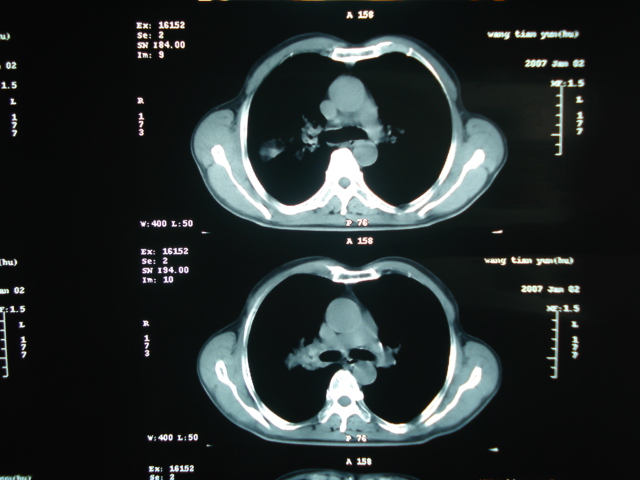

以下是引用狙击手在2007-4-18 20:17:00的发言:[br]原:2007/1/22号ct片:右肺上叶可见片状、云雾状高密度影,右肺上叶后段可见三角形高密度影,尖端指向肺门,右肺上叶后段支气管壁不规则增厚,管腔不规则增厚,纵隔未见肿大淋巴结.[br] 今ct:右肺上叶片状影增大,右肺上叶后段不张及右肺上叶后段支气管壁不规则增厚未见变化,右肺下叶背段支气管壁不规则增厚.[br] 如果考虑肺结核,但从临床证据看竟然没有一项支持肺结核,不知患者是否已经过正规抗结核治疗。没有的话,3个月了前后片看起来变化不大,似乎有不太符合肿瘤征象,不知患者是否抗炎治疗过,下叶支气管增粗还是要高度警惕,同意楼主意见,将常规病理,生化检查再做一遍。[br]

以下是引用狙击手在2007-4-18 20:17:00的发言:[br]原:2007/1/22号ct片:右肺上叶可见片状、云雾状高密度影,右肺上叶后段可见三角形高密度影,尖端指向肺门,右肺上叶后段支气管壁不规则增厚,管腔不规则增厚,纵隔未见肿大淋巴结.[br] 今ct:右肺上叶片状影增大,右肺上叶后段不张及右肺上叶后段支气管壁不规则增厚未见变化,右肺下叶背段支气管壁不规则增厚.[br] 如果考虑肺结核,但从临床证据看竟然没有一项支持肺结核,不知患者是否已经过正规抗结核治疗。没有的话,3个月了前后片看起来变化不大,似乎有不太符合肿瘤征象,不知患者是否抗炎治疗过,下叶支气管增粗还是要高度警惕,同意楼主意见,将常规病理,生化检查在做一遍。[br]